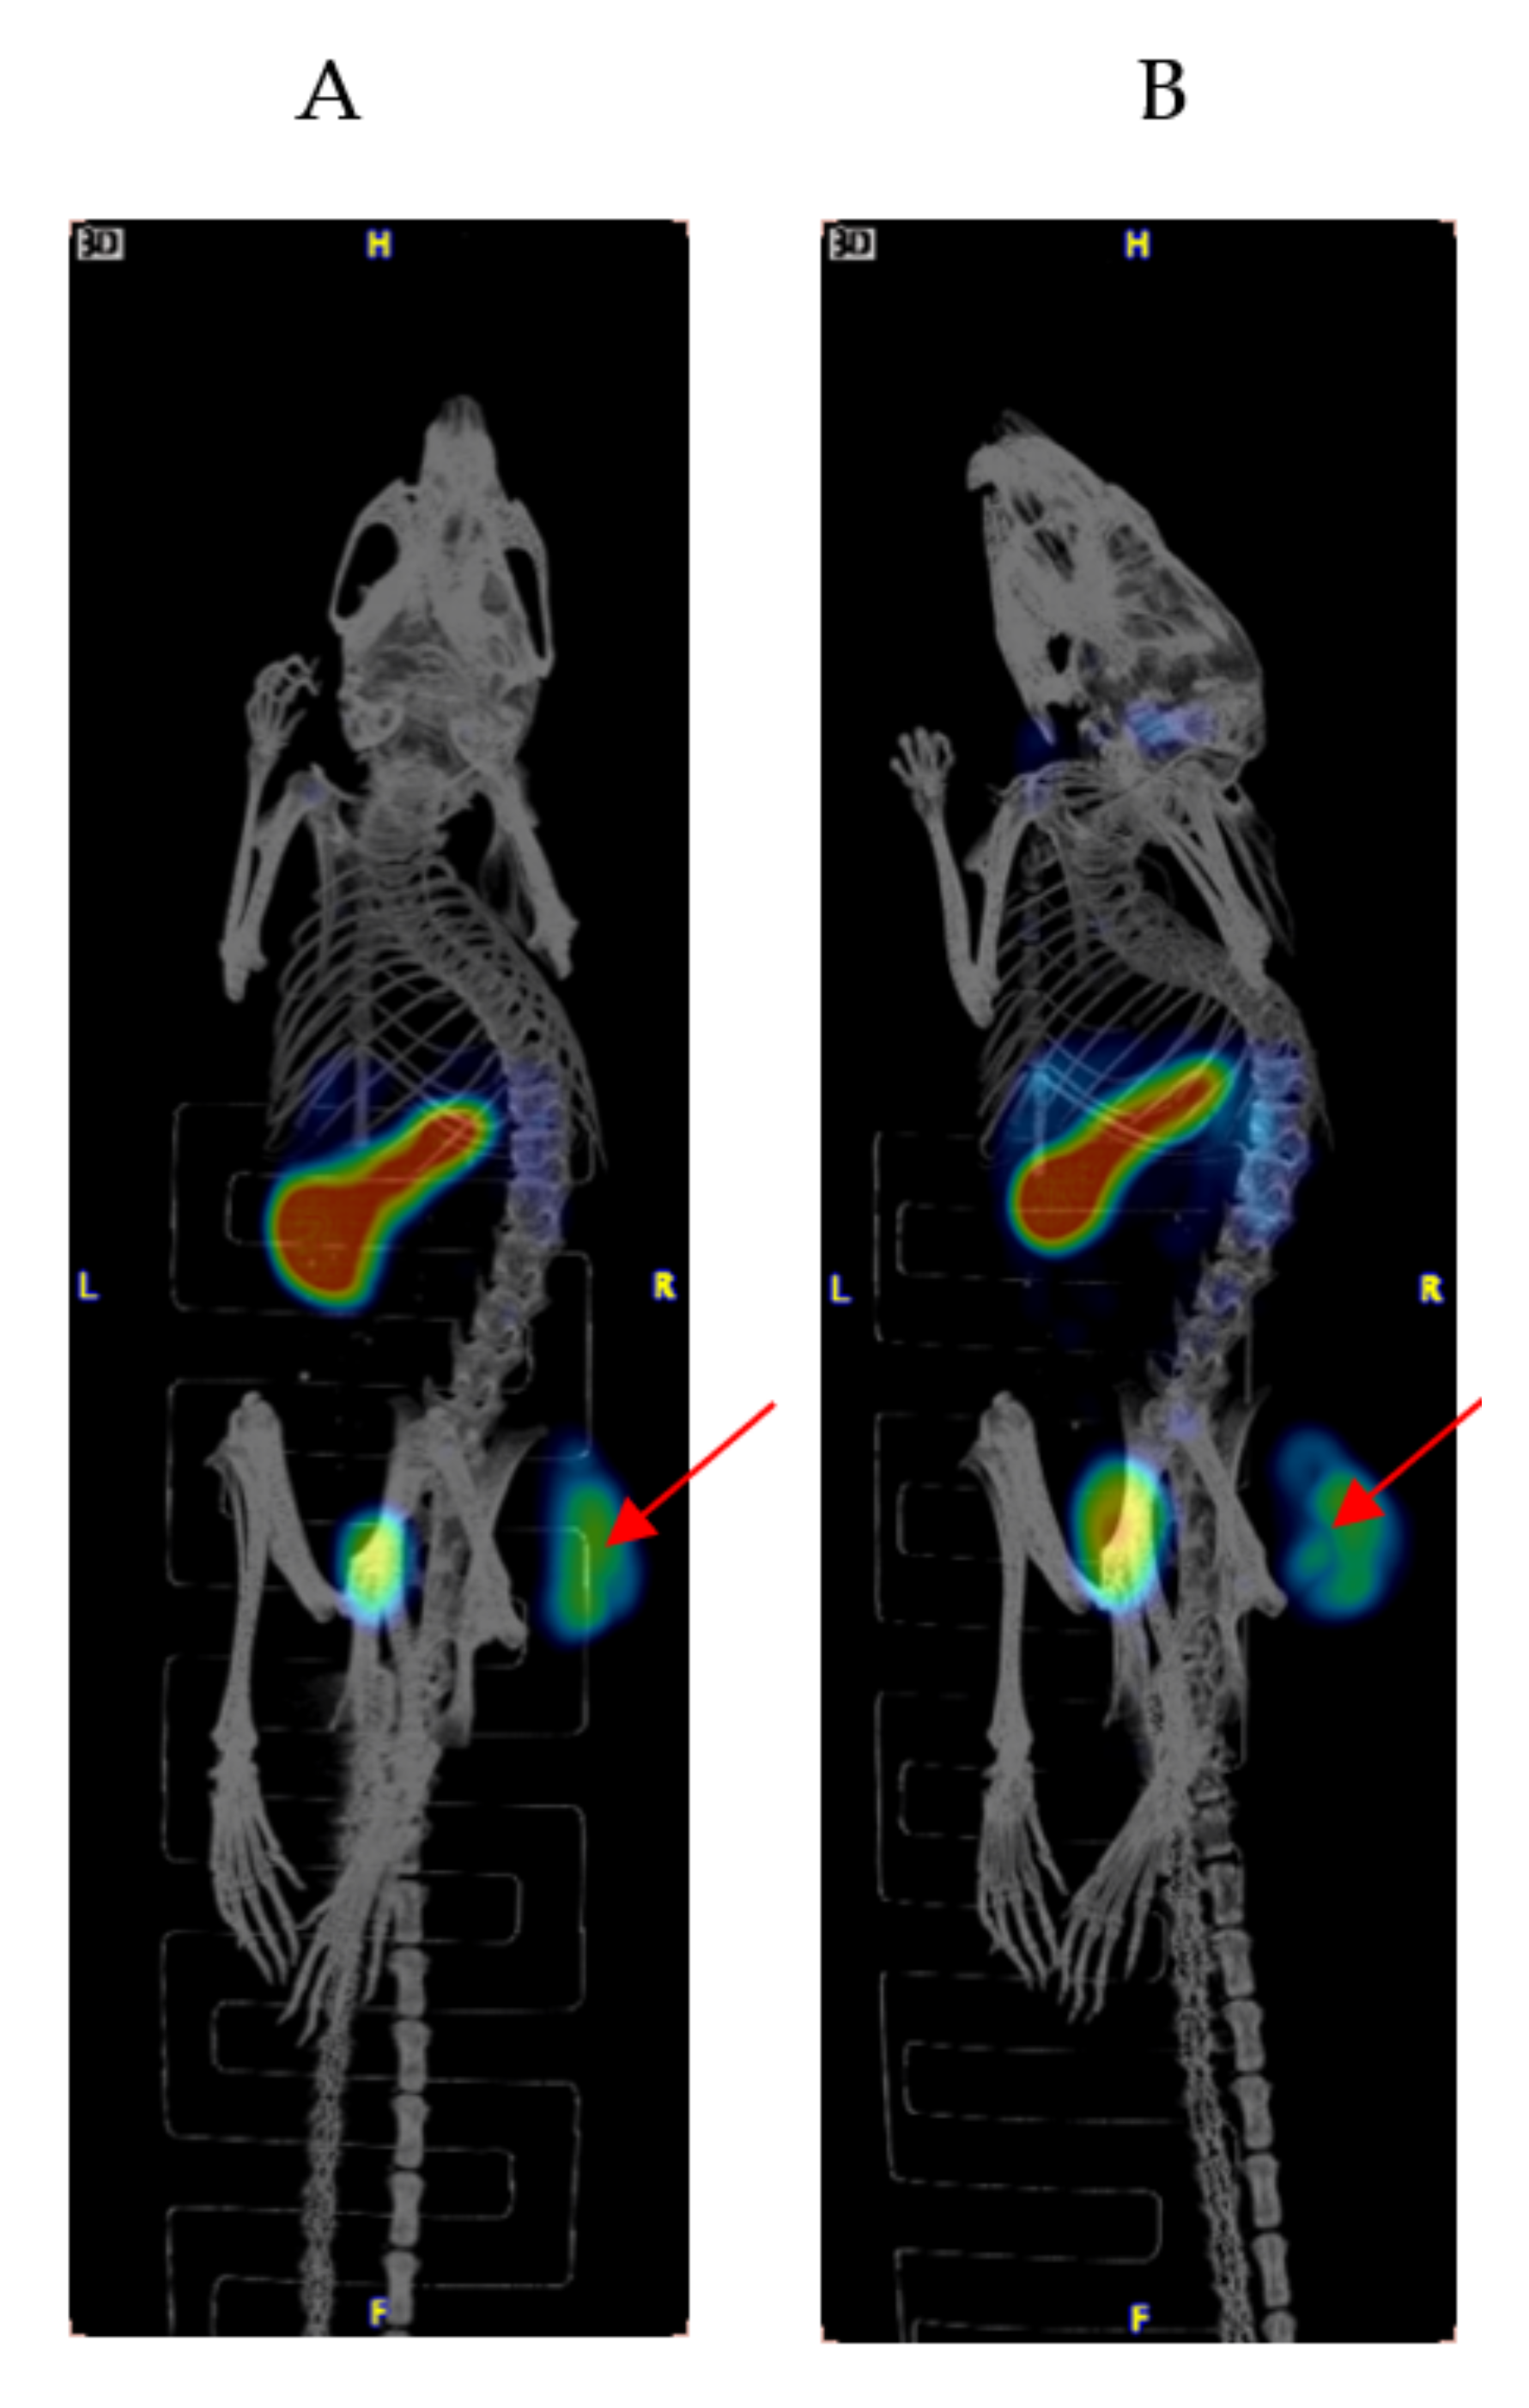

2.1. Biodistribution and Microspect/CT Imaging Demonstrated a High Uptake of the IF3 Antibody in Canine-Patient-Derived Gracie Tumors